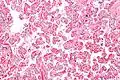

Intermed. mag.

Chorangiosis is a placental pathology characterized by an abundance of blood vessels within the chorionic villi.

It is diagnosed by a microscopic examination of the placenta.

Commonly used criteria from Altshuler[2][3] are: "a minimum of 10 villi, each with 10 or more vascular channels, in 10 or more areas of 3 or more random, non-infarcted placental areas when using a ×10 ocular." The Altshuler criteria are not theoretically rigorous, as they do not define the area. Normal villi have up to five vascular channels.[3]